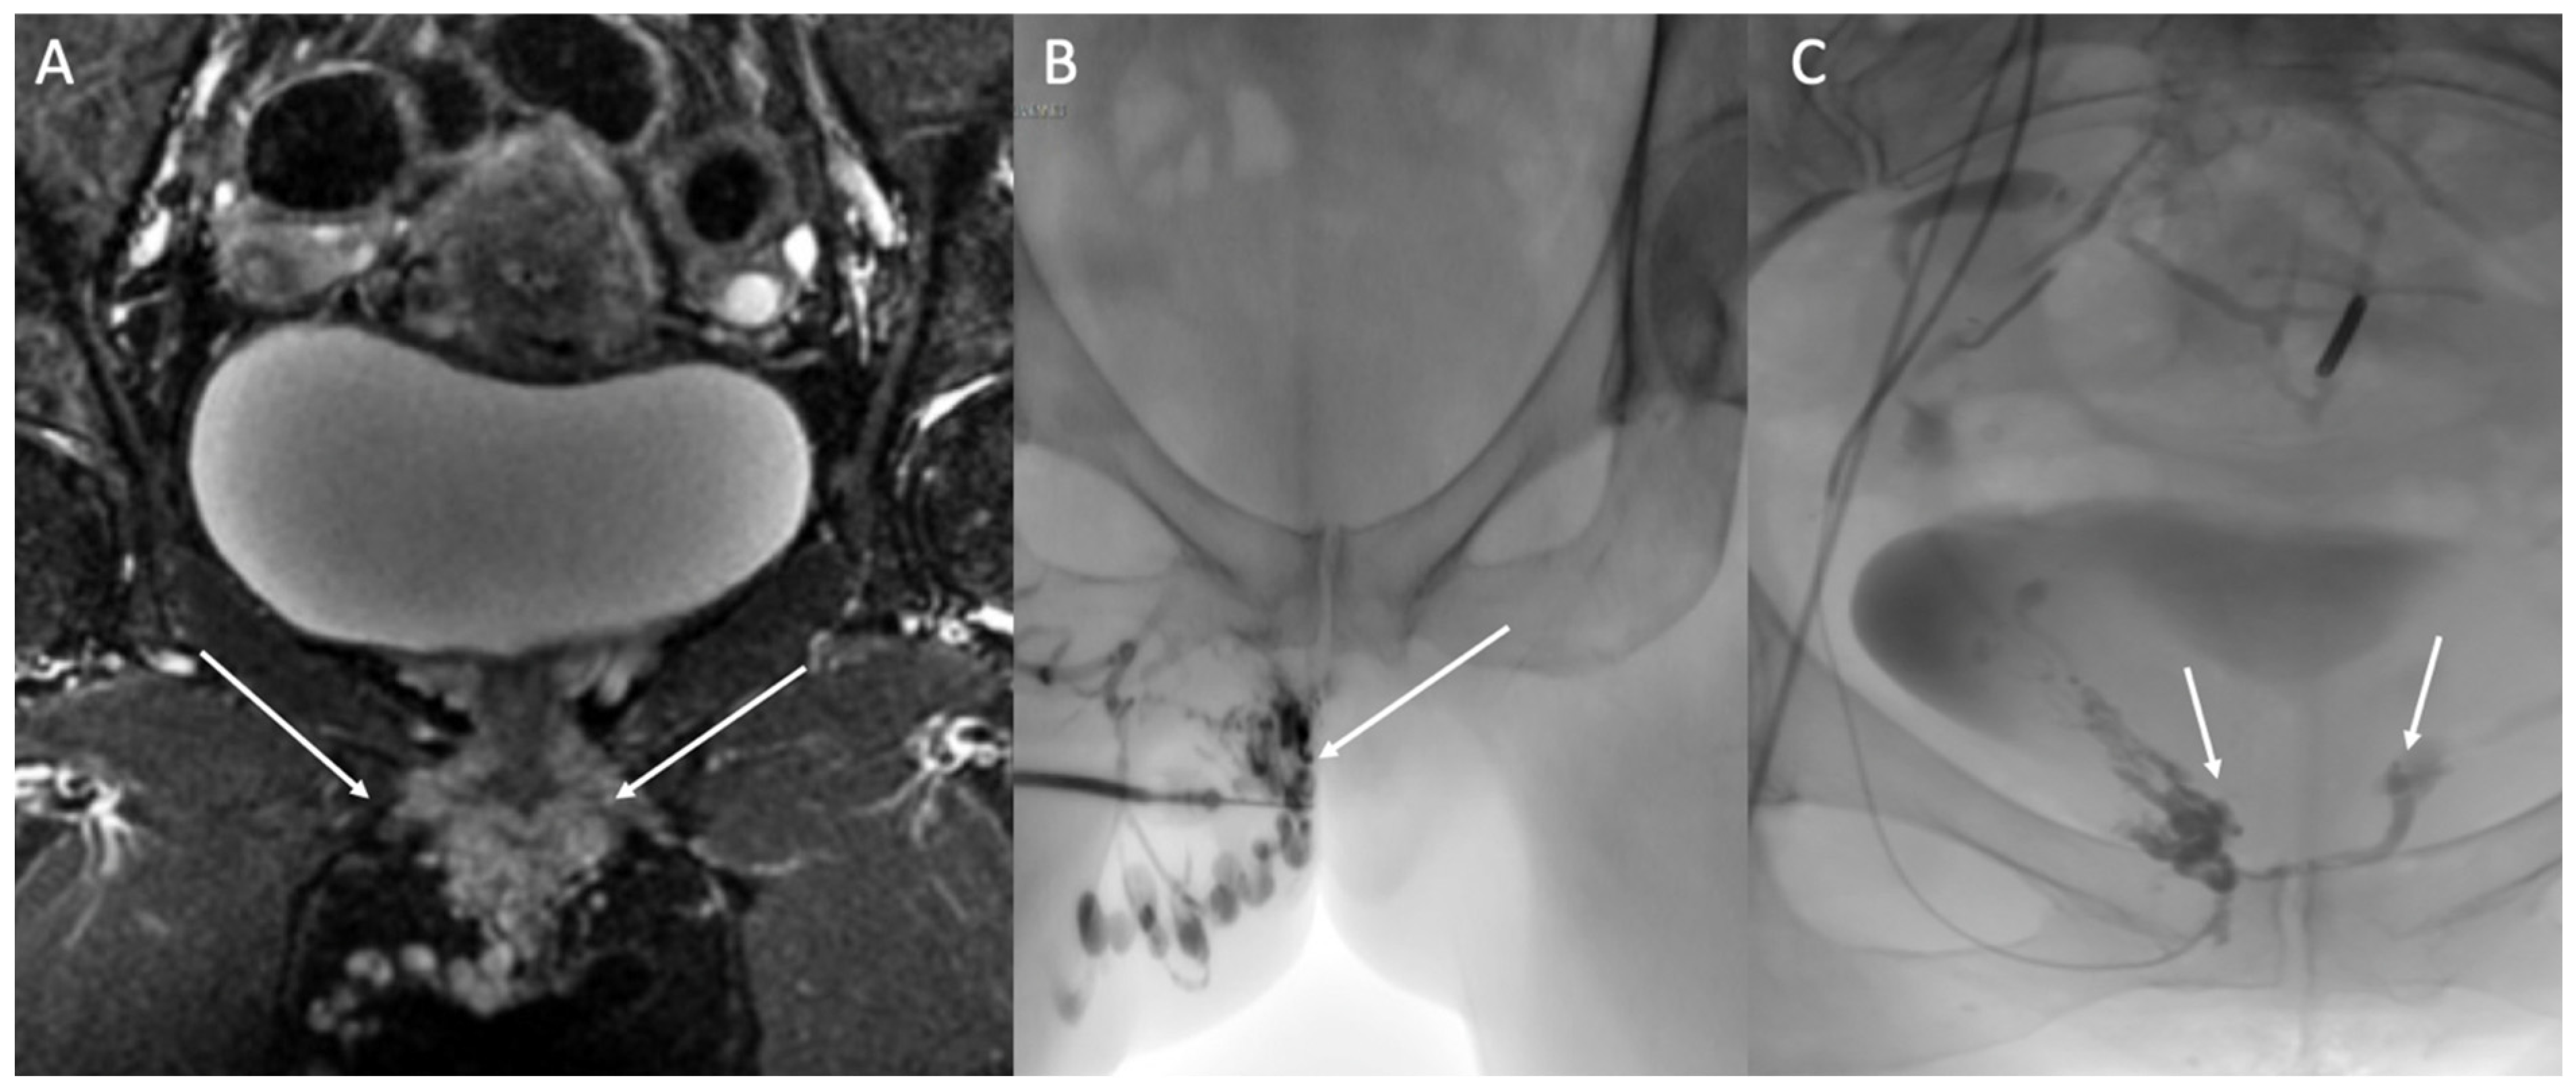

4.3. Vulvar and Lower Limb Varices of Pelvic Origin